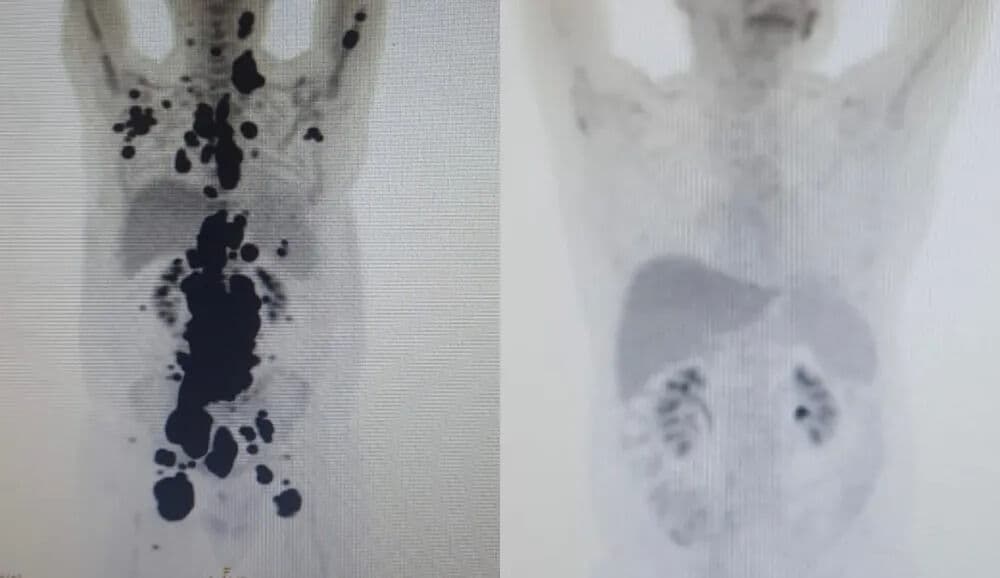

Paciente com câncer há 13 anos tem remissão completa em SP em um mês após terapia celular em estudo na rede pública